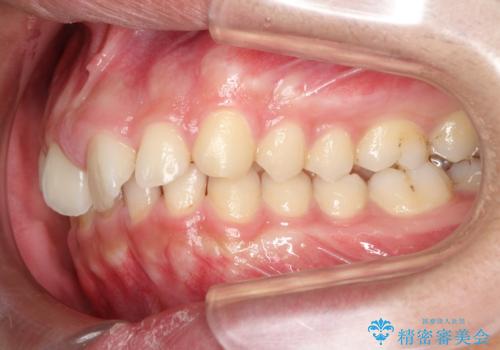

初診時の歯並びの状態としては、上下ともに前歯部の中等度のがたつきがあり、前歯には正中離開があり過蓋咬合を呈してい状態でした。

また奥歯の噛み合わせのズレもあり、特に左は顕著に認められました。